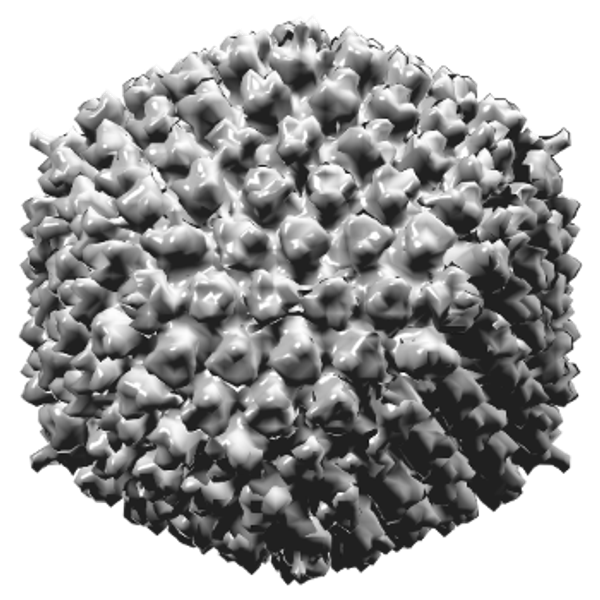

Das Adenovirus ist ein sehr häufiges Erkältungsvirus, das leider nicht mit Medikamenten bekämpft werden kann, da es sich um ein Virus handelt. Das liegt daran, dass ein Virus nur ein kleines Stück genetisches Material ist, das von einer Proteinschicht umgeben ist. Wenn ein Virus in den Körper eindringt, und das geschieht in der Regel durch das Einatmen kleiner Tröpfchen in der Luft, die jemand anderes hustet oder niest, oder durch das Berühren von Oberflächen, auf denen sich das Virus befindet (z. B. Hände, Türklinken und Treppengeländer), setzt es sein genetisches Material in den Zellen frei und veranlasst die Zellen, sich zu vermehren. Das Virus entführt sozusagen die Zelle, und die Zelle selbst beginnt, Virusproteine zu produzieren, die wiederum nach neuen Zellen suchen, die sie befallen können. Auf diese Weise breitet sich das Virus blitzschnell aus.

Ein Virus ist unglaublich klein und daher mit dem bloßen Auge nicht wahrzunehmen. Sie können daher nie feststellen, ob Sie infiziert sind oder ob sich ein Virus in der Luft oder auf einem Gegenstand befindet. Legen Sie ein Virus unter ein Elektronenmikroskop, mit dem Sie es mehr als eine Million Mal vergrößern können, erst dann können Sie das Virus sehen. Zum Vergleich: Ein Virus ist so groß wie ein Fußball auf einem Fußballfeld, das so groß ist wie ganz Europa.

Ein Virus ist so simpel aufgebaut, dass es im Gegensatz zu einem Bakterium nicht eigenständig leben kann. Außerdem können sie nichts von sich aus tun, außer zu warten, bis sie zufällig in einem lebenden Körper mit einer geeigneten Zelle landen, an die sie sich anheften, in sie eindringen und sich dann vermehren können.